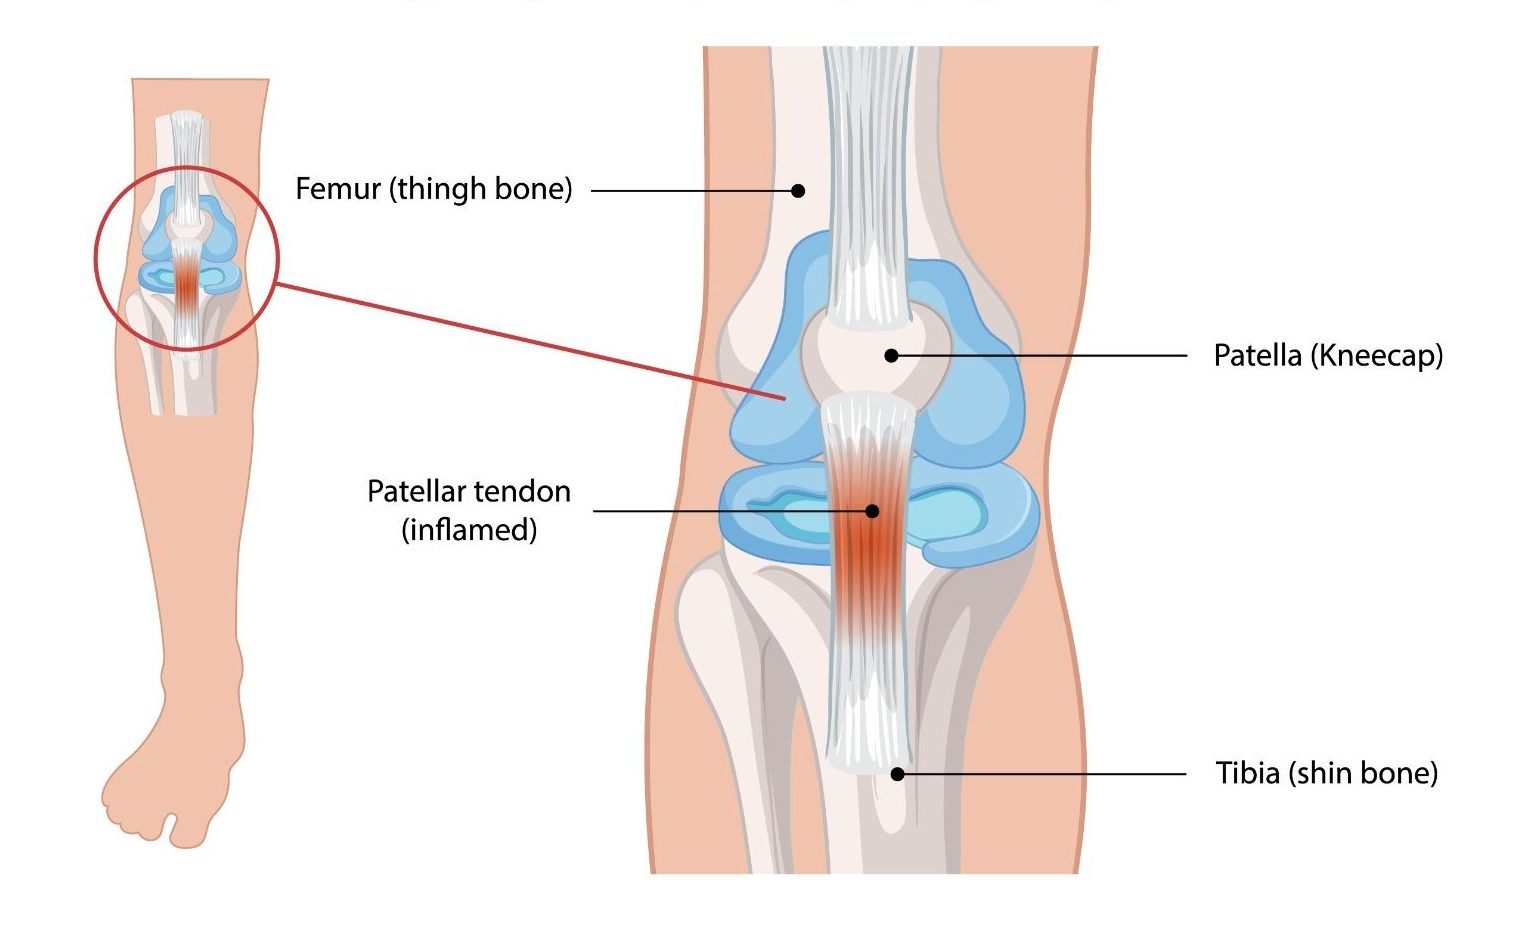

Patellar tendinopathy — commonly known as ‘jumper’s knee’ — is an overuse condition affecting the patellar tendon, which connects the kneecap (patella) to the shinbone (tibia). It is caused by repetitive loading of the tendon beyond its capacity to recover, leading to tendon degeneration, pain, and functional impairment. It is particularly prevalent in jumping athletes — volleyball and basketball players, high jumpers, and footballers — and is one of the most challenging sports injuries to manage due to the tendon’s poor healing response.

- Anterior knee pain localised to the inferior pole of the patella (just below the kneecap)

- Tenderness on pressing the inferior patellar tendon